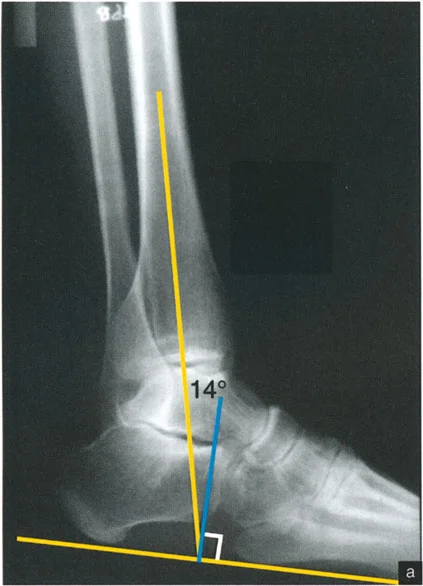

* الأشعة السينية (X-rays) الواقفة لكامل الطرف السفلي: هذه الأشعة ضرورية لتقييم المحاذاة الكلية للطرف السفلي تحت تأثير وزن الجسم. يطلب الأستاذ الدكتور محمد هطيف صورًا شعاعية كاملة الطول للساق أثناء الوقوف (Full-length standing alignment films) لتقييم المحور الميكانيكي للساق وتحديد زوايا المفاصل بدقة.

* الأشعة السينية الجانبية والامامية الخلفية للكاحل: تُظهر هذه الصور تفاصيل مفصل الكاحل نفسه، بما في ذلك زاوية القصبة الأمامية البعيدة (ADTA) وزاوية القصبة الوحشية البعيدة (LDTA)، وهي زوايا حاسمة لتحديد التشوه في المستويين الأمامي والسهمي.